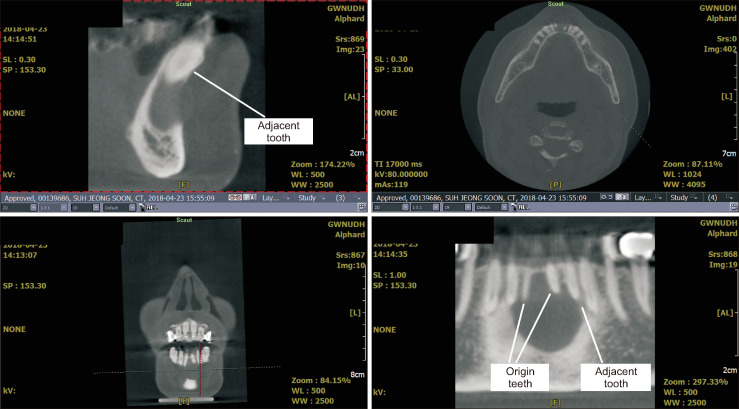

Objectives: Clinical situations that make it challenging to differentiate odontogenic cysts from non-odontogenic cysts and benign tumors of the jaw include cases with cystic conditions accompanied by secondary infection, impacted teeth, cortical thinning and expansion, or external root resorption. This study aimed to identify risk factors for complications in patients undergoing cyst enucleation of the jaw, propose a clinical model, and determine the necessary indications for preoperative root canal of adjacent teeth.

Materials and methods: A review of surgical, pathological, and radiological reports, as well as medical records, was conducted. Pathological diagnosis, lesion size, history of preoperative endodontic treatment of the adjacent tooth, operator details, surgical procedures, age, gender, and complications (with severity) were analyzed.